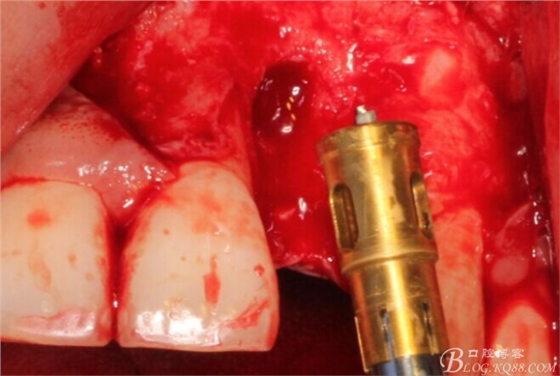

于是我果斷告知患者,手術(shù)失敗了,不能拖延,如不及時(shí)處理,炎癥繼續(xù)發(fā)展會(huì)很快波及鄰牙牙槽骨。患者接受我的建議。切開翻瓣,骨粉及生物膜消失了,骨吸收嚴(yán)重,幸運(yùn)的是,因?yàn)樘幚砑皶r(shí),鄰牙骨支持依然存在。

徹底掻刮。